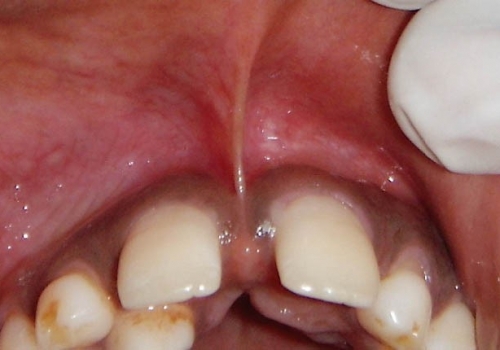

Frenulum (yüyən), diş əti toxuması (gingiva) ilə dil, dodaq və yanaq arasında yerləşən, toxumaları bir-birnə bağlayaraq hərəkətlərini sərhədləndirən yumuşaq selikli qişa toxumasıdır. Frenulum normal ölçülərdən böyük və qalın olduqda və ya diş əti kənarına yaxın yerləşdikdə bəzi narahatlıqlara və məhdudiyyətlətə səbəb ola bilir. Diş əti çəkilməsi, estetik məhdudiyyət, diastema, çıxan protez istifadə edən şəxslərdə protez fiksasiyasının məhdudlaşması və s. durumlar bununla bağlı ola bilir.